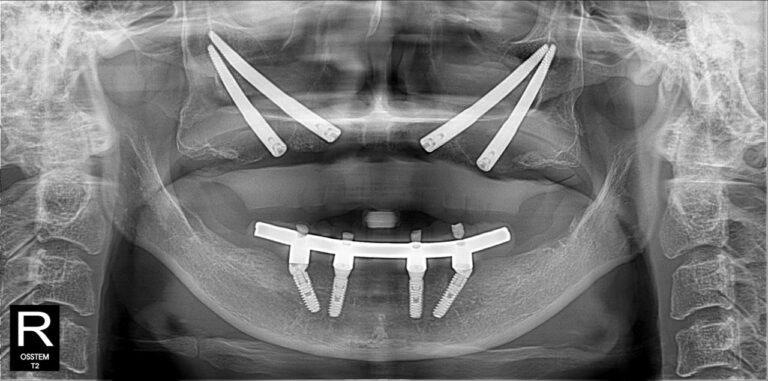

Không nằm ở lời nói mà thể hiện qua kết quả điều trị thực tế. Những hình ảnh X-quang dưới đây là sự khẳng định cho năng lực phẫu thuật và sự chính xác tuyệt đối của BS CKI Nguyễn Trung Khánh trong các ca đại phẫu thuật Implant nhiều lần cắm.

All-on-4/All-on-6 là kỹ thuật phục hồi nhiều răng/toàn hàm bằng cách đặt 4 hoặc 6 trụ implant 1 lần trồng răng